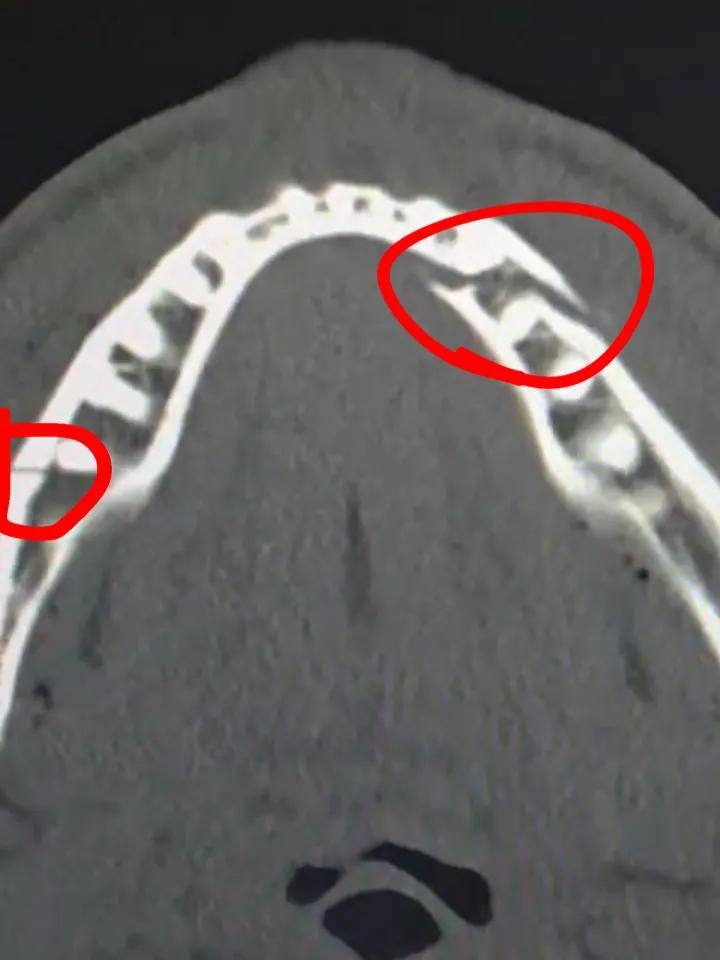

Kayla Mcconnell+FollowJake Paul’s brutal double jaw break vs JoshuaJake Paul walked away from his fight with Anthony Joshua not just with a loss, but with a double broken jaw—spitting blood right in the ring after a thunderous knockout. Even after being knocked down four times, Paul kept his spirits up, joking with fans and sharing his X-rays online. The fight itself left a lot of viewers disappointed, with many saying the action was slow and even calling it “rigged.” Still, Paul is already calling for another big-name opponent. What do you think—should he get another shot, or is it time to hang up the gloves? #Sports #Wrestling #JakePaul00Share